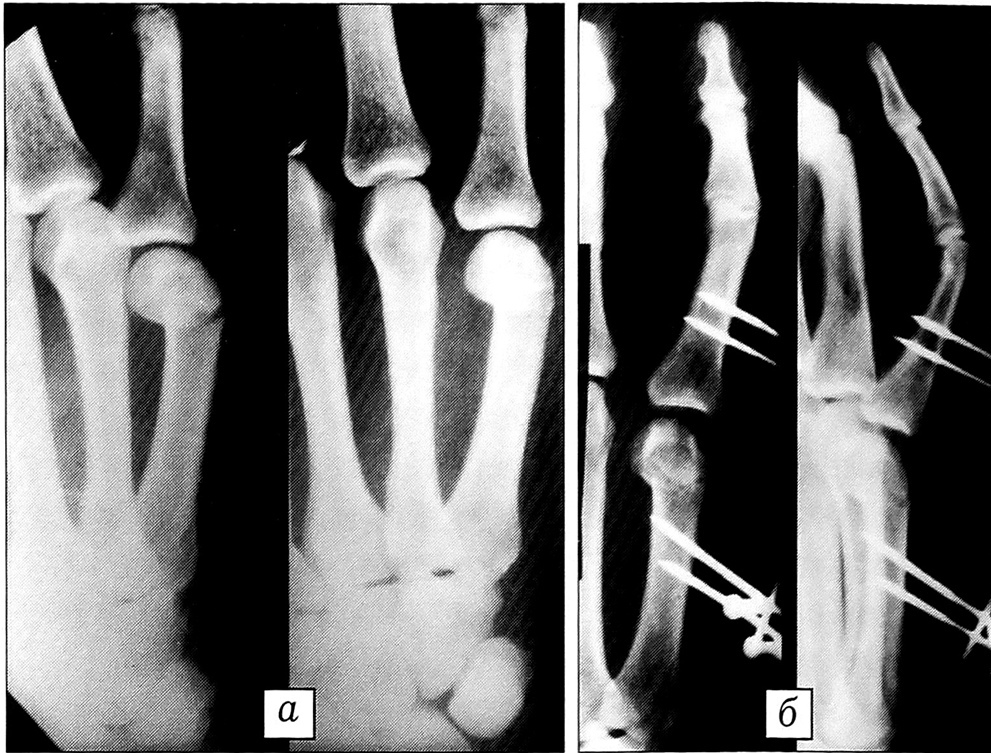

После наложения аппарата осуществляли умеренную дистракцию (2~3 оборота дистрактора) и выполняли обычную закрытую мануальную репозицию дистального отломка по известной методике [5]. Производили контрольную рентгенографию и при приемлемом стоянии отломков отпускали больного на амбулаторное лечение. На 4-5-й день после операции повторяли контрольную рентгенографию с целью выявления и предупреждения перерастяжения отломков. Один раз в 10 дней больной самостоятельно осуществлял 0,25 оборота дистрактора. Со 2-го дня после операции пациенту предлагали выполнять легкие активно-пассивные движения в межфаланговых суставах пальца. Аппарат демонтировали через 3—4 нед при наличии клинических и рентгенологических признаков сращения перелома (см. рисунок). Назначали реабилитационную терапию.

Рентгенограммы больного с закрытым несвежим (10 дней после травмы) переломом шейки V пястной кости со смещением отломков.a — при поступлении; б — перед демонтажом стержневого аппарата наружной фиксации.